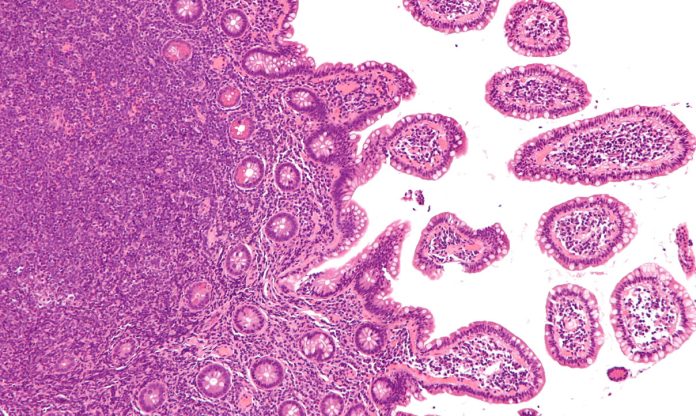

Αυτή η εικόνα δεν έχει ιδιότητα alt. Το όνομα του αρχείου είναι 7-12.jpg

Τ λέμφωμα τύπου εντεροπάθειας: Αυτό το λέμφωμα εμφανίζεται σε άτομα με ακραία ευαισθησία στη γλουτένη, που είναι η κύρια πρωτεΐνη στο αλεύρι σίτου. Οι άνθρωποι με την ασθένεια αυτή, που ονομάζεται εντεροπάθεια από ευαισθησία στη γλουτένη (κοιλιοκάκη), μπορούν να αναπτύξουν λέμφωμα στα τοιχώματα του εντέρου. Πιστεύεται, ότι αν η νόσος ανακαλυφθεί γρήγορα, η δίαιτα ελεύθερη γλουτένης μπορεί να βοηθήσει στην πρόληψη του λεμφώματος, αλλά και στην εξέλιξή του.